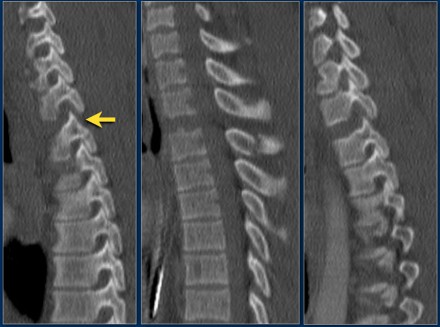

The findings are:

- The main feature is posterior distraction with horizontal fractures of posterior elements (red arrow)

- Avulsion of a spinous process (yellow arrow)

- Widening of facet joint (green arrow)

- Burst-type fracture

In this case some would call this a burst fracture with PLC-injury i.e. 2+3 points.

However the distraction is the most important finding, i.e. distraction and PLC injury, i.e. 4+3 points.

- Morphology: Distraction- 4 points

- PLC: always disrupted in distraction on posterior side - 3 points

- TLICS: 7 points